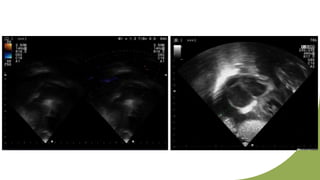

16/M

42/M

31/M